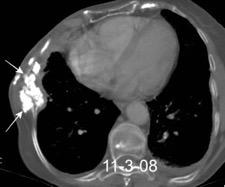

40. EMPIEMA PLEURAL. ORIGEN HEPÁTICO

Colecciones “inflamatorias” abdominales llegan al tórax vía el hiato esofágico o por vía transdiafragmática

Afectación transdiafragmática: 5,6-43,7% de quistes hepáticos. “Área desnuda” del hígado.

Panda A et al. “Straddling Across Boundaries”. Thoracoabdominal Lesions: Spectrum and Pattern Approach. Curr Probl Diagn Radiol. 2015 Área desnuda. El hígado en contacto directo con el tendón central del diafragma. Contiene el hiato de VCI.